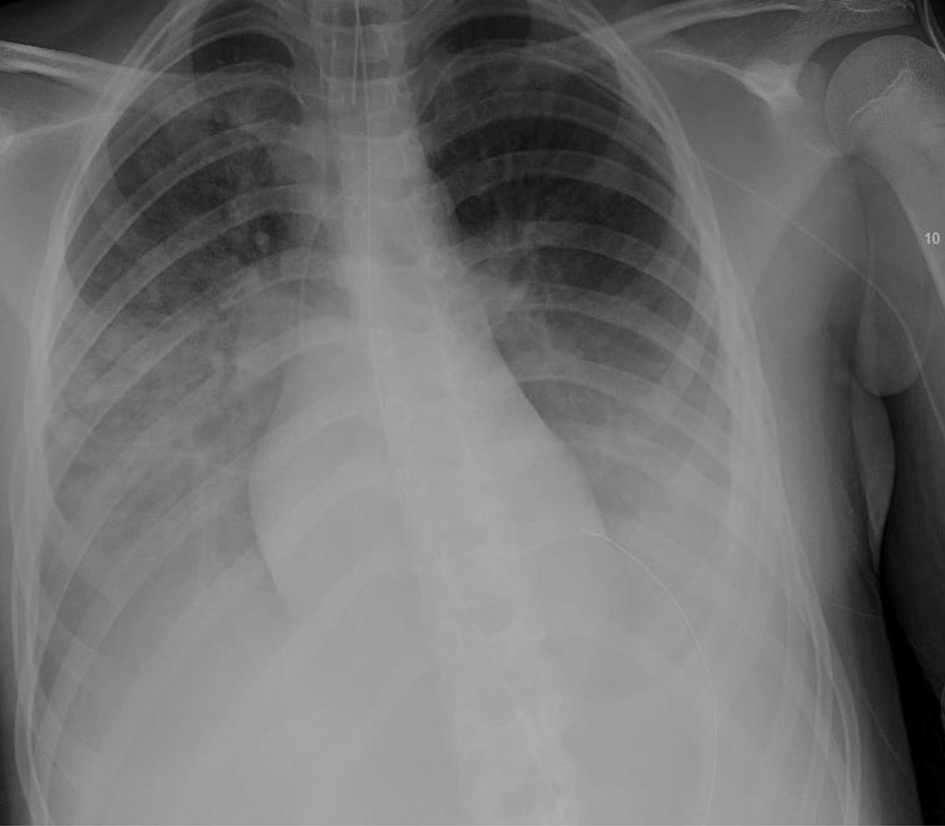

Radiographic imaging revealed significant bilateral parahilar and basilar airspace opacities (right greater than left) consistent with pneumonia and atelectasis, as well as a right pleural effusion (Figs. 1, 2).

![]() Click for large image | Figure 1. Chest X-ray, anteroposterior (AP) view on third presentation to emergency department showing signs of pneumonia with consolidation. |